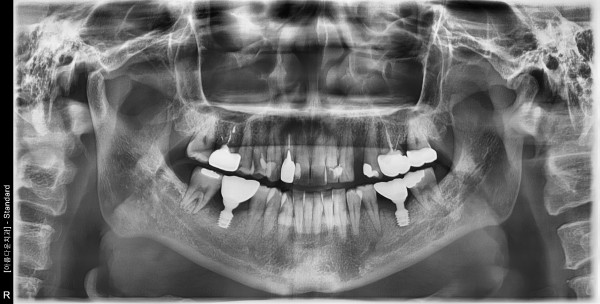

47세 남자 상하악 구치부 뼈 이식후 임플란트 식립